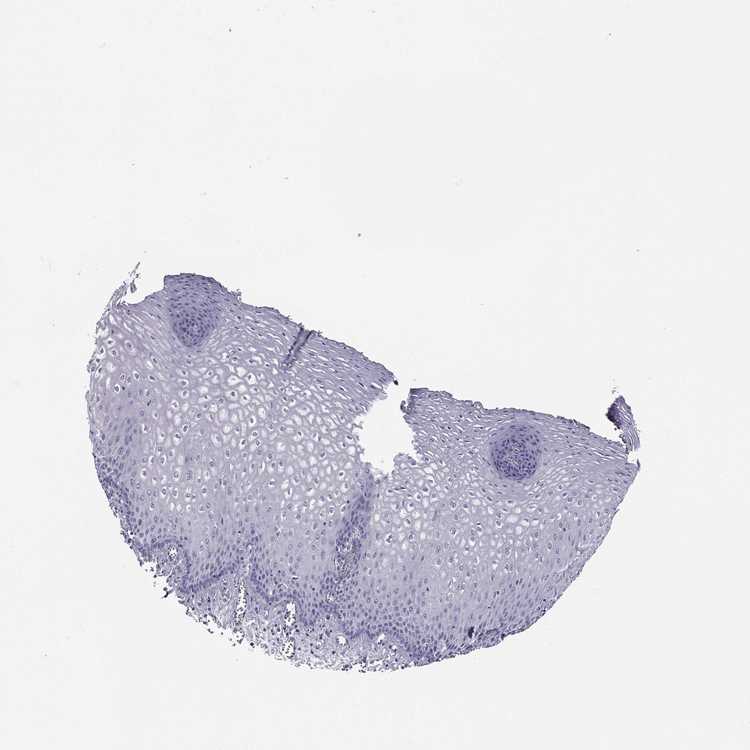

ESOPHAGUS - Antibody stainingi

Antibody staining in the annotated cell types in the current human tissue is reported as not detected, low, medium, or high, based on conventional immunohistochemistry profiling in selected tissues. This score is based on the combination of the staining intensity and fraction of stained cells.

Each image is clickable and will lead to virtual microscopy that enables deeper exploration of all samples and also displays staining intensity scores, fraction scores and subcellular localization as well as patient and tissue information for each sample.

Antibody HPA006135Antibody HPA071007

Squamous epithelial cells Not detectedNot detected